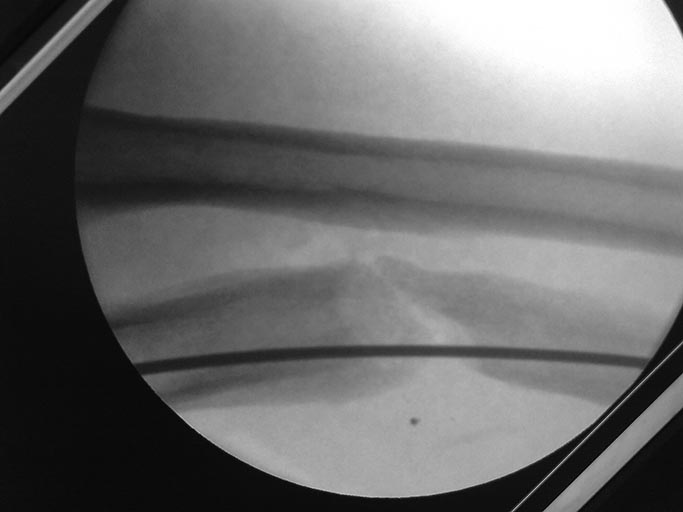

Вчера больной прооперирован головку лучевой кости пришлось

резцировать(сгибание было около 100 гр.и все бы ничего, но ось локтевой

кости очень плохо выравнивалась ,сгибание после резекции увеличилось на

20 гр.)Снимок после резекции головки.